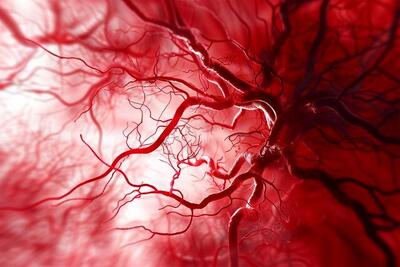

رگها را پس از سکته ترمیم می شوند

این ساختار سه بعدی مولکولهای درمانی را پس از سکته به مغز میرساند.